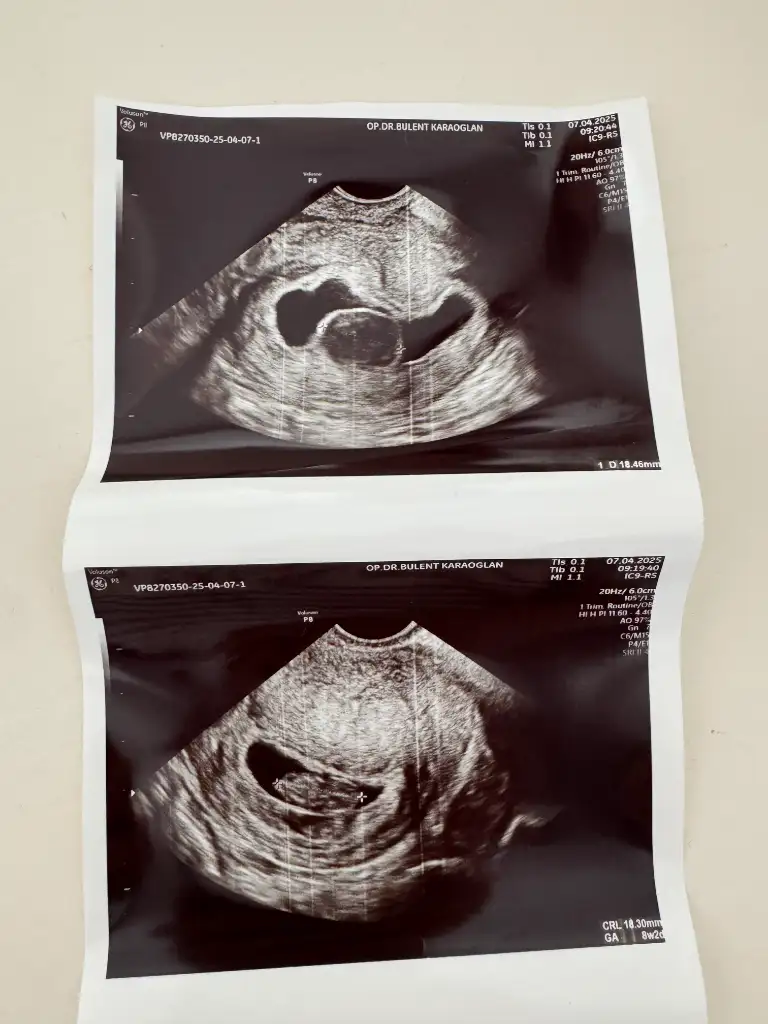

çok küçük ama kese kız gibiBana da yorum yapar mısınız 8 haftalık vajinal bakıldı

Ayy insallah ağzınız bal yesinçok küçük ama kese kız gibi

Bunlarada bakabilir misiniz

bacak arası görüntü anlamıyorum canımBunlarada bakabilir misiniz